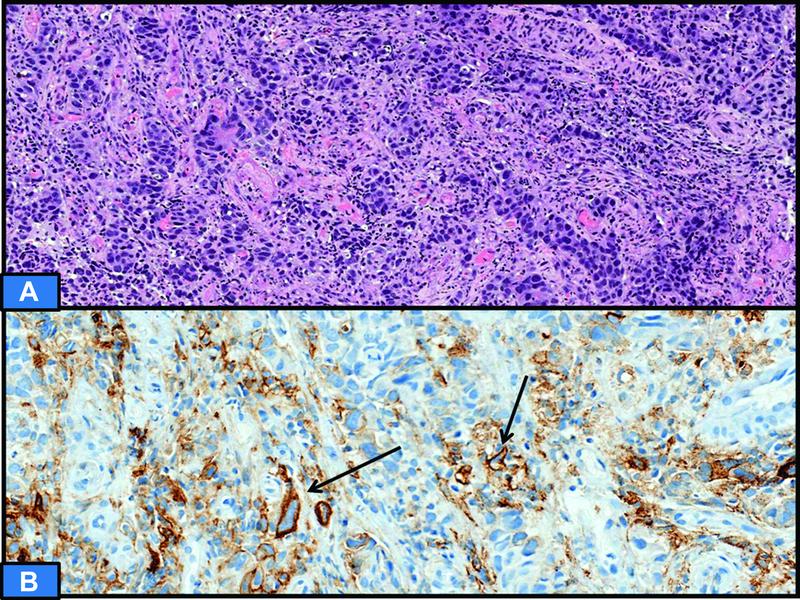

| Figure 4: (A) Hematoxylin and eosin section showing poorly differentiated adenocarcinoma of stomach. (B) Programmed cell death protein ligand 1 (PD-L1) immunohistochemistry showing CPS of 40. The high score is attributed to immune cells displaying PD-L1 staining, while very few tumor cells show membranous positivity (arrow).

Combined Positive Score (CPS): It is scored as number of PD-L1-stained cells (tumor cells, lymphocytes, macrophages) divided by the total number of viable tumor cells, multiplied by 100. It is expressed in numbers and not in percentage, as it may exceed 100. CPS is frequently utilized for metastatic and recurrent head and neck squamous cell carcinoma as well as metastatic gastric/gastroesophageal adenocarcinoma ([Fig. 4]).